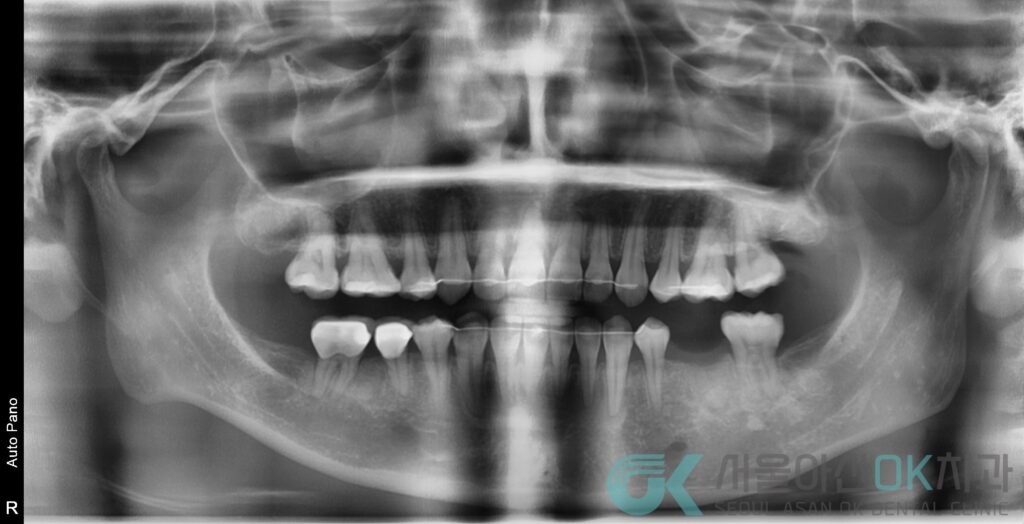

- 영상 판독 : #36 치근단 병소(Imp. 치근단병소)

- 임상 소견 : 부종(염증성), 협측 골 소실이 진행된 상태로 기록

즉, #36은 염증으로 뼈가 녹아 심을 자리(골)가 부족해진 상태였고,

단순 발치로 끝내면 향후 임플란트가 더 어려워질 가능성이 큰 케이스였습니다.